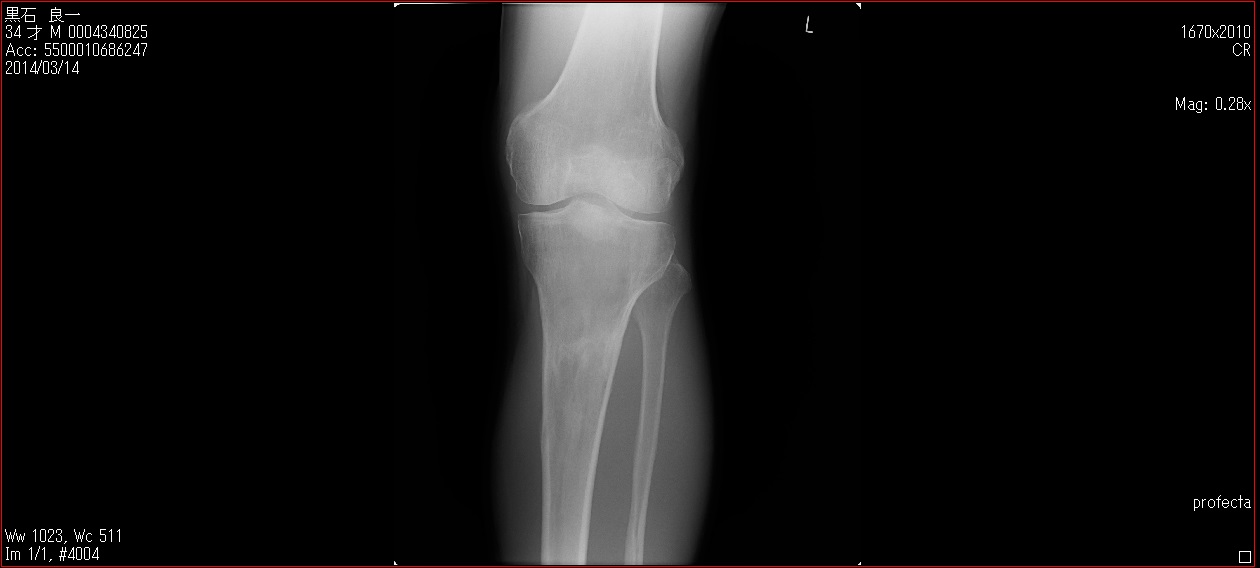

[Ortho] patella baja

Пациент 27 лет приехал для удлинения роста по эстетическим показаниям. Метод: крослатеральное двухэтапное удлинение голеней 4см и бедер 3 см.  Между этапами удлинения уезжал к себе домой в Японию на реабилитацию. Между этапами удлинения движения в коленных суставах разгибание полное сгибание 90-85. После выписки (февраль 2012) даны соответствующие указание постепенно возрастающей нагрузки и ЛФК коленных суставов.

В настоящий момент жалобы на ограничение сгибания в коленных суставах. Снимки прилагаются.

Вопрос: почему возникло такое осложнение? Поверьте приходилось удлинять намного больше, а тут всего на 3-4 см и такое осложнение на обеих конечностях у одного пациента?

Что можно сделать? У кого есть опыт лечения patella baja?